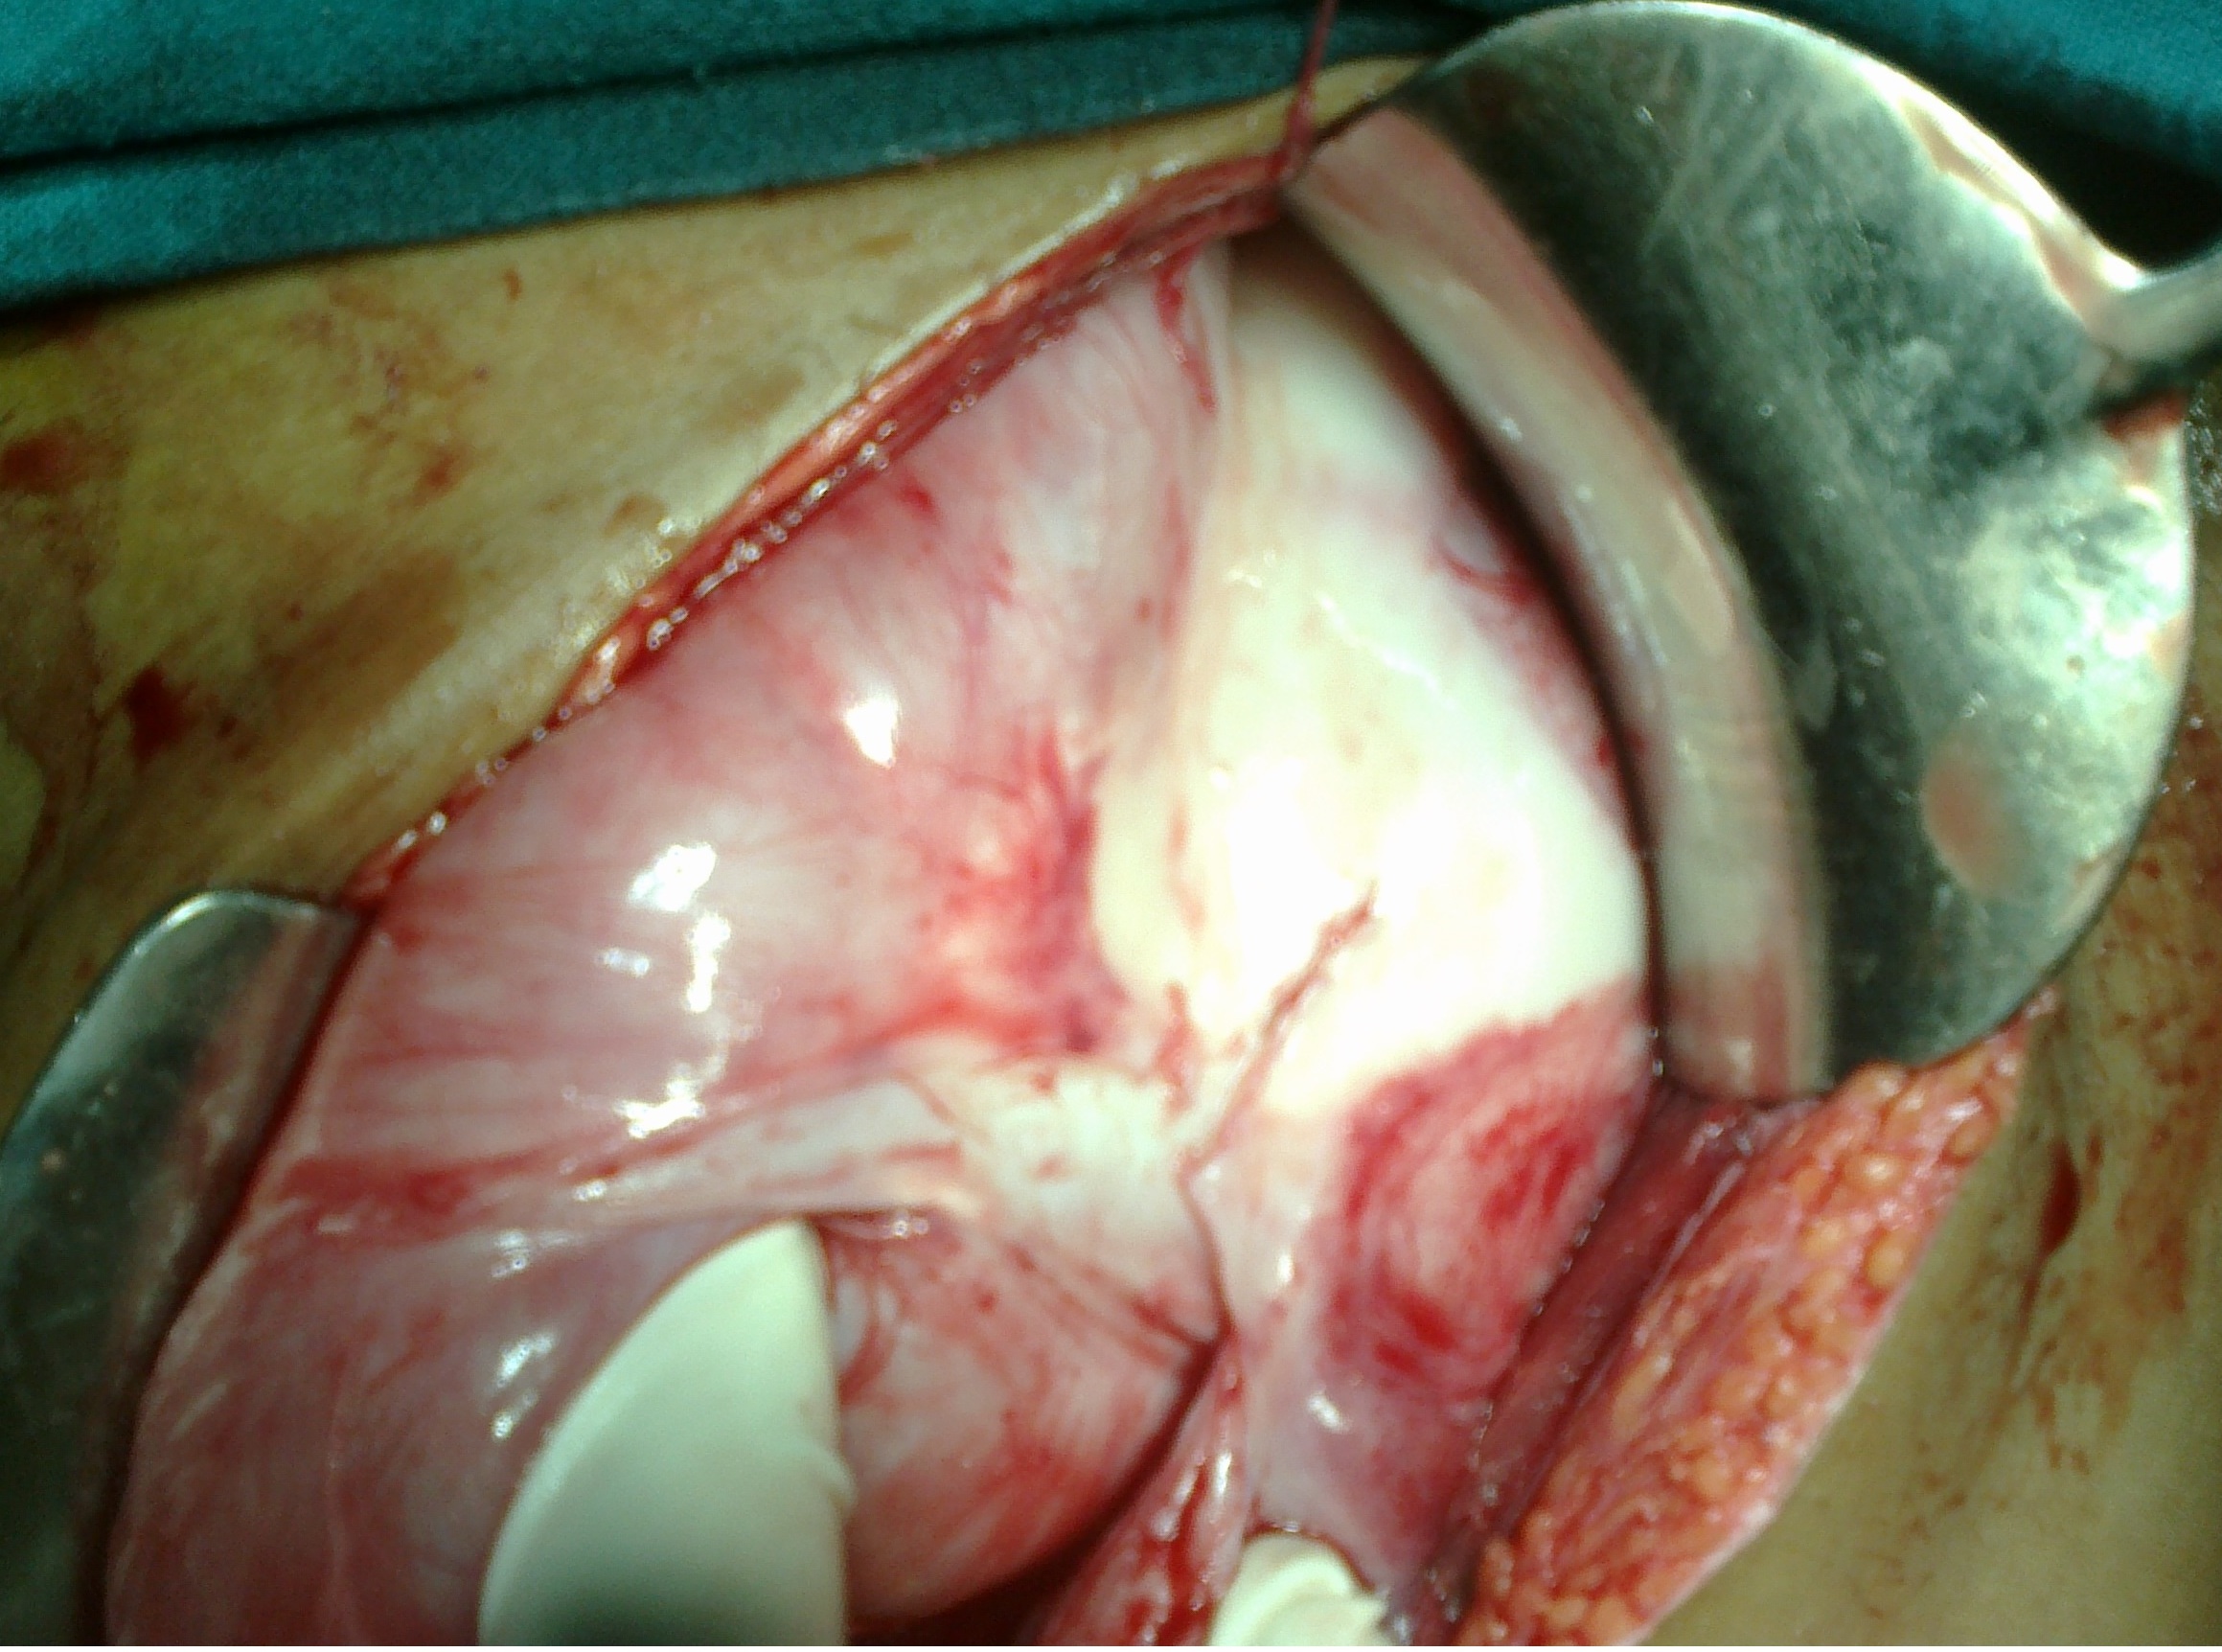

Results. A total of 17 patients presented to the emergency ward with features of acute intestinal obstruction. The average age was 15.3 years (range 9 years to 16 years). There were 14 females and 3 males. All patients presented with abdominal pain, bilious vomiting, constipation and abdominal distention. The patients were operated in our hospital and relieved of their obstruction. Based on their operative findings and after histopathological confirmation, patients were given ATT. In the follow-up, all patients did well, without recurrence of tuberculosis or intestinal obstruction.

Conclusion. Tuberculosis as a cause of childhood AC is rather common in developing countries and is potentially a fatal condition. A strong clinical suspicion, sonographic and computed tomography scan findings help establish a pre-operative diagnosis. Tuberculous AC has a strong prevalence in females. Surgery is the mainstay of treatment followed by anti-tuberculous drugs.